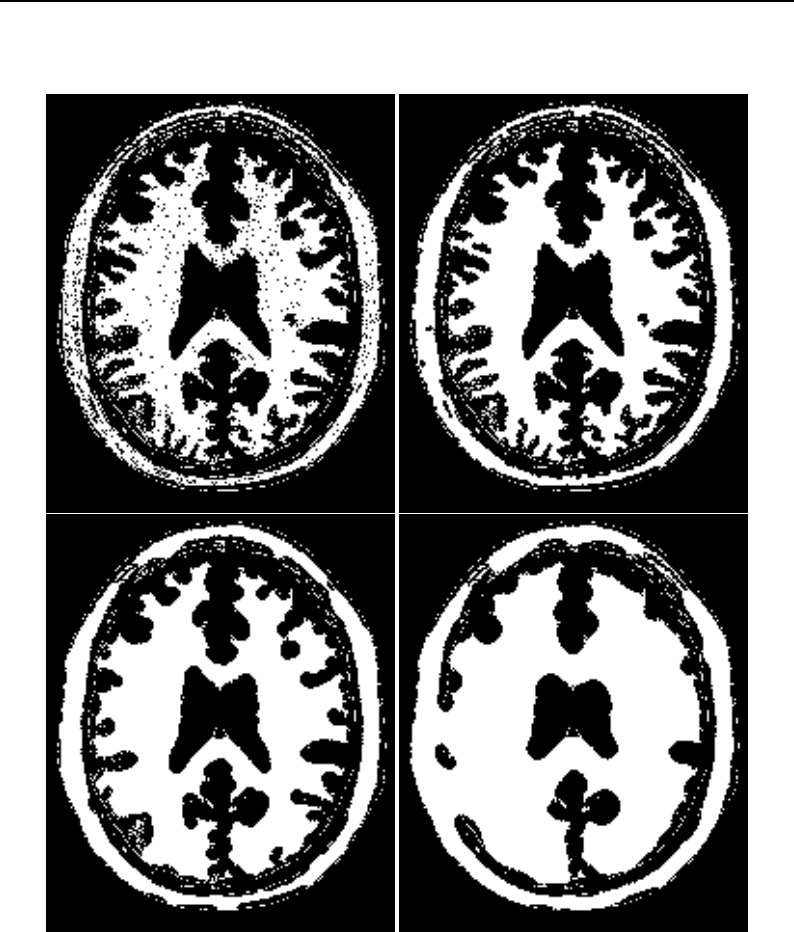

The National Library of Medicine Insight Segmentation and Registration Toolkit, shortened as the

Insight Toolkit (ITK), is an open-source software toolkit for performing registration and segmenta-

tion. Segmentation is the process of identifying and classifying data found in a digitally sampled

representation. Typically the sampled representation is an image acquired from such medical instru-

mentation as CT or MRI scanners. Registration is the task of aligning or developing correspondences

between data. For example, in the medical environment, a CT scan may be aligned with a MRI scan

in order to combine the information contained in both.